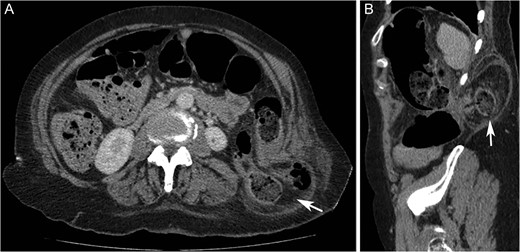

A 72-year-old woman presented with acute lower abdominal pain and nausea. She had not opened her bowels in 5 days and was passing no flatus. Her medical background included Parkinson’s Disease, hypothyroidism, hypertension, pulmonary embolism and deep vein thrombosis. Further history revealed a longstanding swelling in her left flank, diagnosed as a lipoma and excised 15 years ago under local anaesthetic. Interestingly, according to the patient, her swelling was unchanged after the procedure. A community ultrasound done over a year before her acute presentation had suggested the presence of a hernia (Fig. 1); however, the sonographer was not a musculoskeletal specialist and could not confirm the diagnosis. Biopsy only showed subcutaneous fatty tissue and the lump was diagnosed as a recurrent lipoma.

Ultrasound scan of the left flank showing possible hernia in a 72-year-old woman presenting with a flank swelling (dashed line).